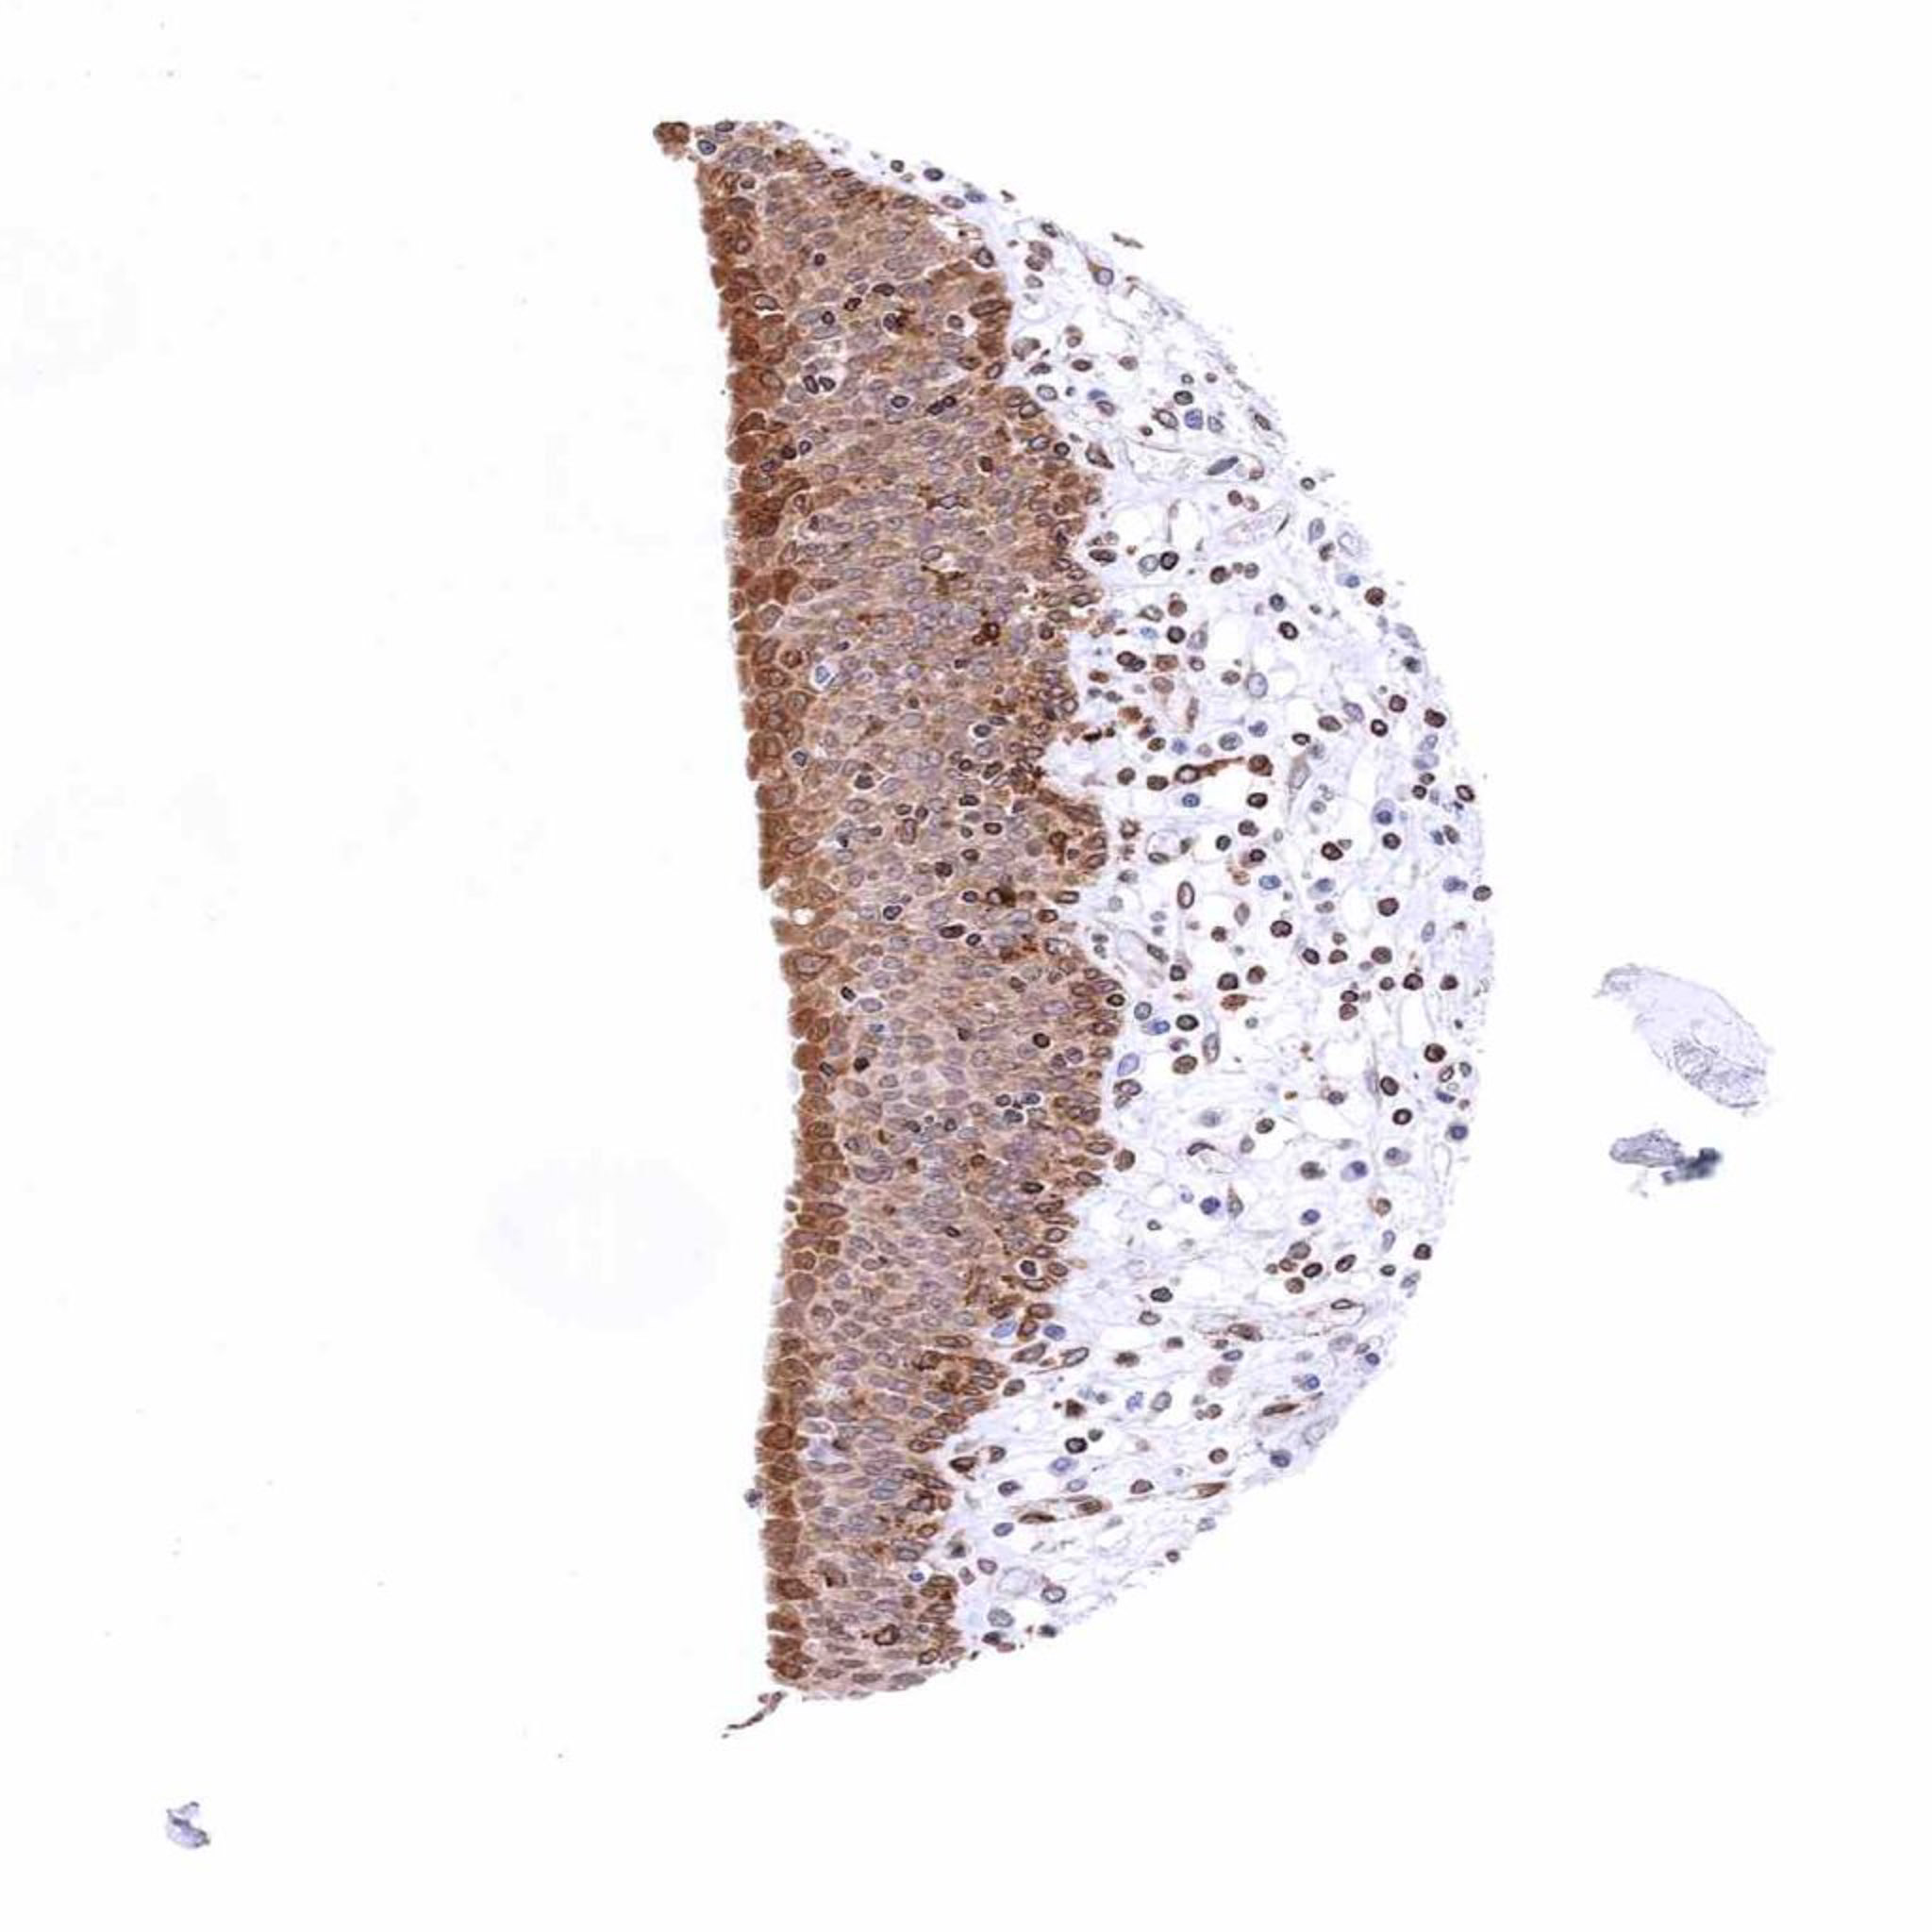

Tonsil, surface epithelium – Strong STING staining of all cell layers of the squamous epithelium (STING immunohistochemistry)